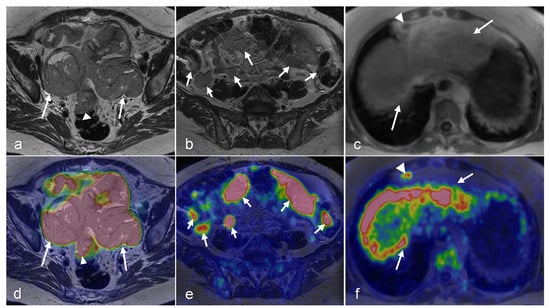

3.3. Ovarian Cancer

3.4. Vaginal and Vulvar Cancers